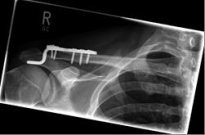

Picture 1                                                                Picture 2

Picture 2: After the operation, the fracture is correctly repositioned and held in position with a titanium plate and two screws..